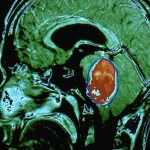

They, in turn, form the upper layers of the telencephalon, are located next to the base, inside the body of the white area, due to which they are called the basal (subcortical) nuclei. They also include the amygdala and striatum. The gray-white area is essentially the subcortical part of the teleencephalon and the main input base of the basal ganglia system. In sections taken horizontally or frontally, the striatum appears as an alternation of gray and white stripes, which is why it was called the striatum.

Striatum consists of two parts:

- Dorsal (posterior) region. Placed externally, it includes both the caudate and lenticular segments, as well as the shell.

- The ventral (anterior) region, which consists only of the nucleus accumbens. Layers of white matter divide it into segments: the medial globus pallidus, the putamen of the lenticular area, and the lateral globus pallidus.

In primates, the striatum is divided into the ventral striatum and the dorsal striatum, subdivisions based on function and connections. The ventral striatum includes accumbens cells and the olfactory tubercle. The dorsal striatum includes only the caudate nucleus and putamen. White matter, a nerve tract (internal capsule) in the dorsal striatum separates the caudate region from the putamen. Anatomically, the term striatum describes the striped appearance of the grey-white matter.

The dorsal striatum forms a continuous large mass, topographically separated by the internal capsule in the caudal segment medially, the putamen on the side and the floor below, connecting the two preceding ones ventrally into a single whole. The striatum is homogeneous in its neuronal components.